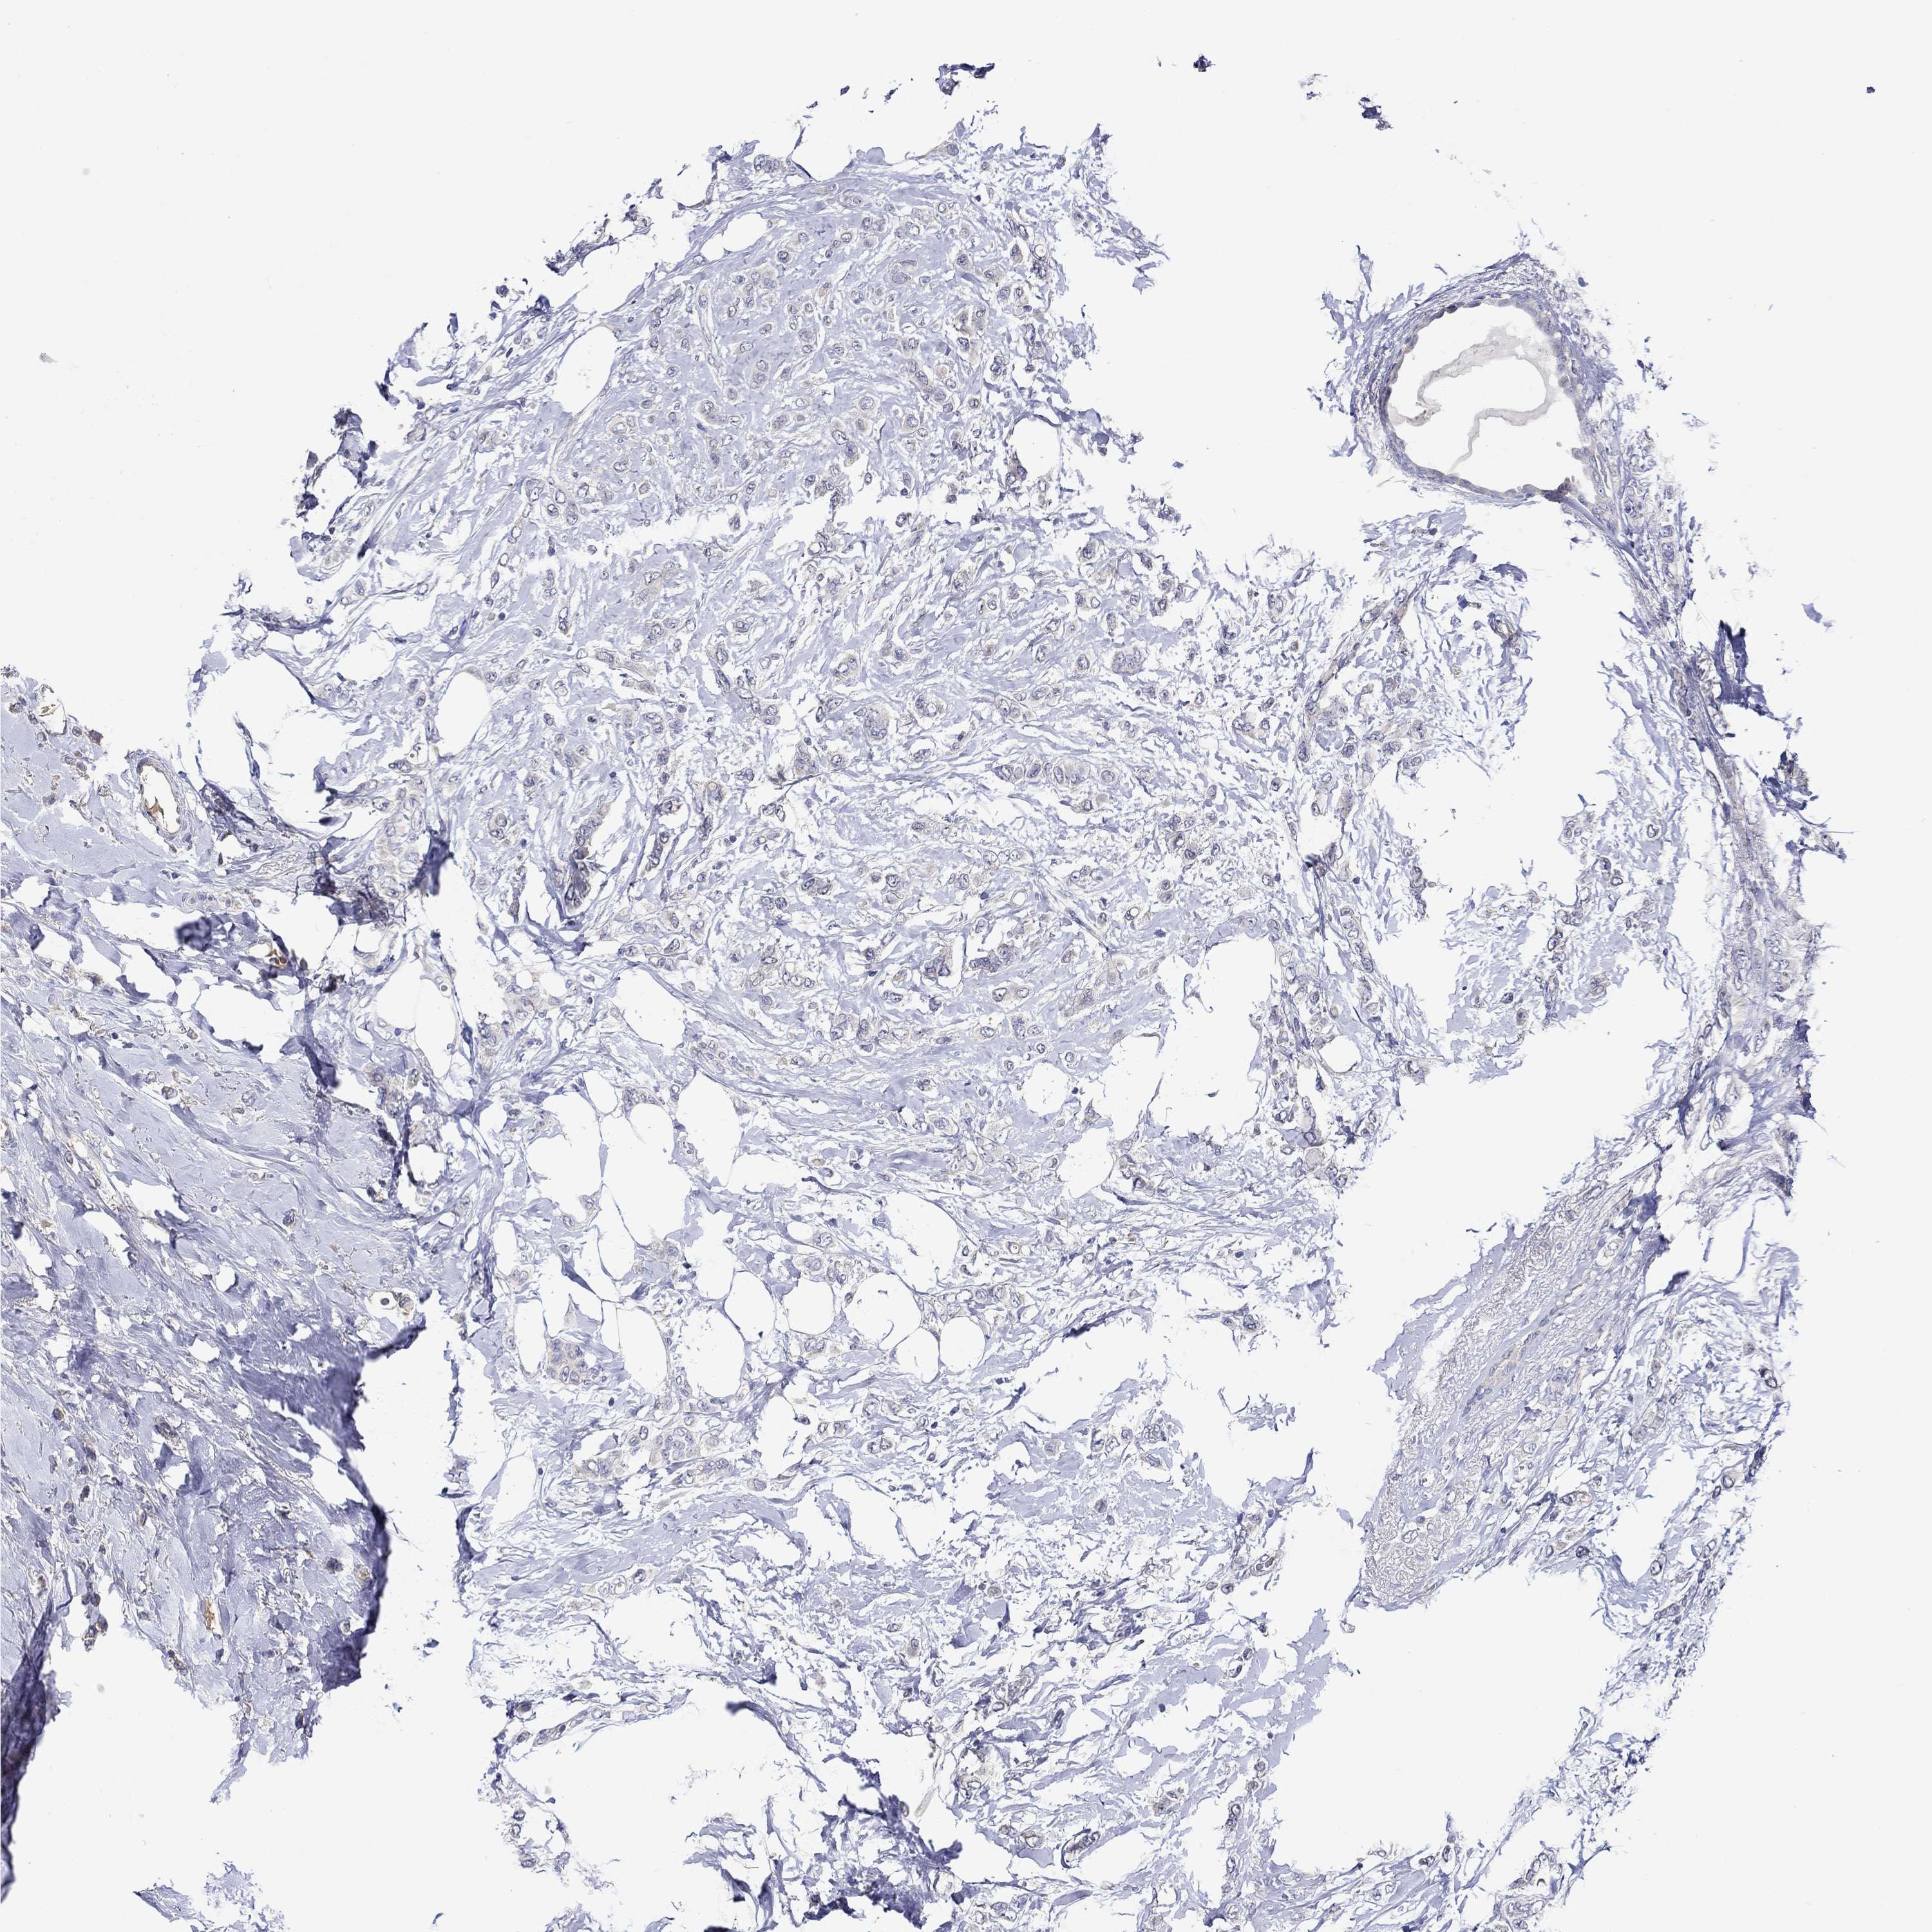

BRCA TCGA BRCA VALIDATION PROTEIN EXPRESSION